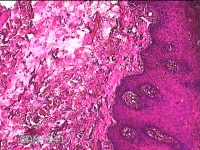

右侧颊部粘膜肿物

性别

女

年龄

48岁

临床诊断

口腔黏膜粘液囊肿

一般病史

右侧颊部粘膜长肿物2月余。

标本名称

大体所见

灰白粉红色囊性肿物0.8x0.7x0.3cm一个,表面光滑,部分已切开,内容物已流失,囊壁厚0.1cm。